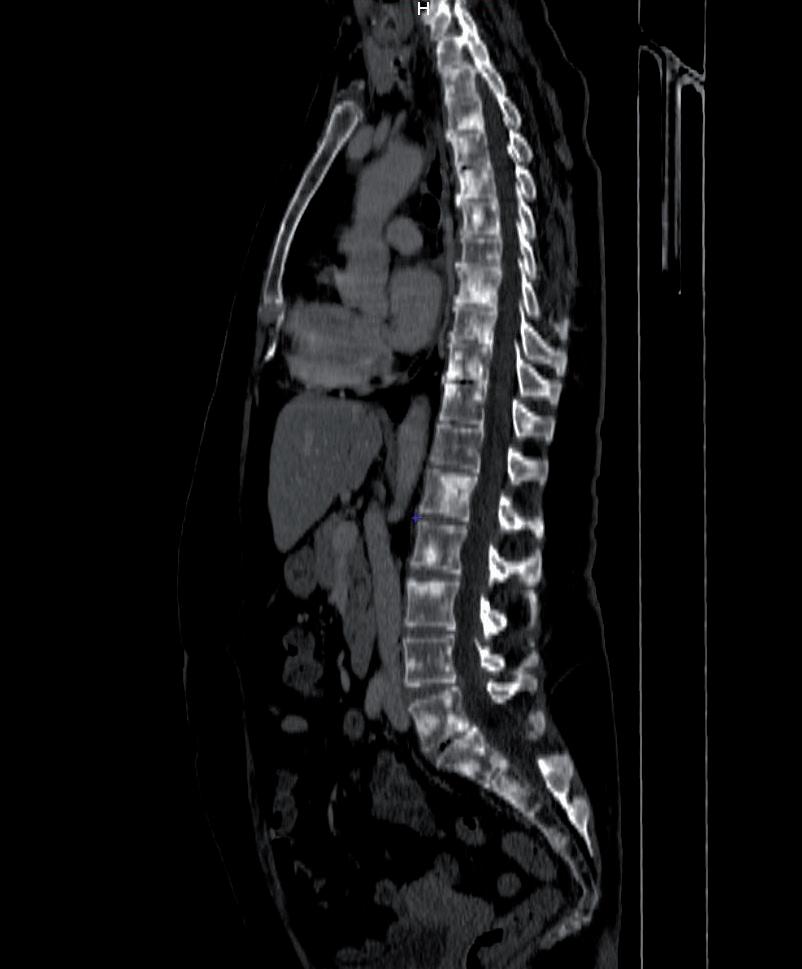

Con la PET/TC eseguita a novembre del 2016 si evidenziava la presenza di significative alterazioni di distribuzione del radiofarmaco a carico del fegato e a livello scheletrico, come da alterazioni di natura sostitutiva. In particolare, in corrispondenza del fegato, si segnalava significativa captazione focale a livello del settimo segmento e altra poco più cranialmente. Si evidenziavano poi plurime significative captazioni estese a tutto il rachide cervicale, dorsale e lombare (SuvMax fino a 18) oltre che a tutto il bacino, oltre che a livello delle coste bilateralmente, clavicola sx, manubrio sternale, entrambe le scapole, entrambe le teste e diafisi prossimali omerali, diafisi omerale destra, entrambi i femori a livello delle teste, delle regioni trocanteriche, maggiormente a sx, diafisi prossimali femorali, corrispettivo alle immagini TC ad alterazioni addensanti, in parte ad alterazioni litiche, in parte a malattia ancora in fase pre-radiologica (figura 1).

1. TC/PET TB, novembre 2016.

Figura